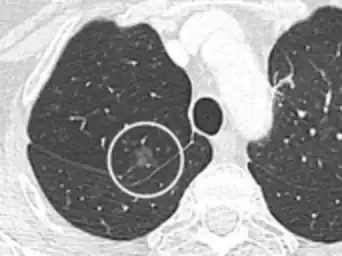

Thin slice and maximal intensity projection of a lung nodule, the latter better visualizing vascular convergence.[9]

• Vascular convergence is where vessels converge to a nodule without adjoining or contacting the edge of the nodule, and is mainly seen in peripheral subsolid lung cancers.[9] It reflects angiogenesis.[9]

Air bronchograms is defined as a pattern of air-filled bronchi on a background of airless lung, and may be seen in both benign and malignant nodules, but certain patterns thereof may help in risk stratification.[9]